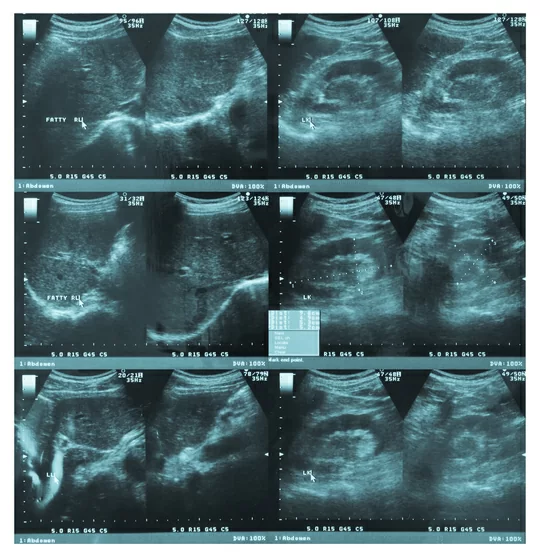

Одним из важнейших критериев — или ультразвуковых маркеров — при диагностировании синдрома Дауна у эмбрионов является толщина воротникового пространства (ТВП). У любого плода на сроке 11-14 недель можно ее измерить. Было замечено, что у 75% эмбрионов с синдромом Дауна ТВП больше, чем у обычных плодов. Позже были открыты не менее важные ультразвуковые маркеры: длина носовых костей, оценка кровотока в венозном протоке и на трикуспидальном клапане.

Комбинированный скрининг в первом триместре позволяет заподозрить патологию плода. Это вспомогательный метод, целью которого является выявление группы риска на основе ультразвуковых и биохимических маркеров. У 75% плодов с синдромом Дауна может быть расширено воротниковое пространство, у 25% оно будет нормальное. У 35-40% плодов с хромосомной патологией наблюдается аномальный венозный кровоток — у остальных он будет нормальный. Поэтому нужна комплексная оценка. Чем больше маркеров рассматривается, тем больше вероятность правильного заключения по этому эмбриону. По-прежнему во всем мире идет поиск новых маркеров. Все врачи пренатальной ультразвуковой диагностики очень этим озабочены, каждый год появляются новые исследования на эту тему.

Врач-генетик анализирует уровень сывороточных маркеров, собирает анамнез, анализирует ультразвуковое исследование и, возможно, назначает повторный ультразвук у врача экспертного уровня. Если высокий риск присутствия хромосомной патологии подтверждается, следующий этап — это инвазивная пренатальная диагностика. В зависимости от срока беременности выделяют хорионбиопсию (на сроке от 11 до 15 недель) и амниоцентез.